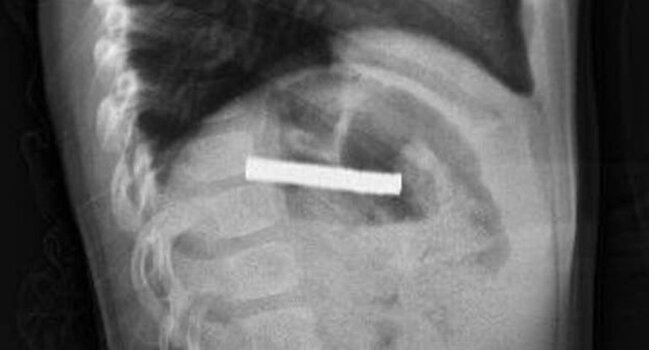

Türkiyədə 3 yaşlı uşağın boğazından 19 ədəd maqnit çıxarılıb.

Ölkə.az xəbər verir ki, Ərzurumda uşaq evdə tapılan 19 maqniti udub.

Fırat Universitetinin Uşaq Qastroenterologiyası, Hepatologiya və Qidalanma kafedrasının müdiri Prof.Dr.Yaşar Doğan endoskopik üsulla uşağın qida borusuna ilişib qalmış 19 maqniti çıxarıb.